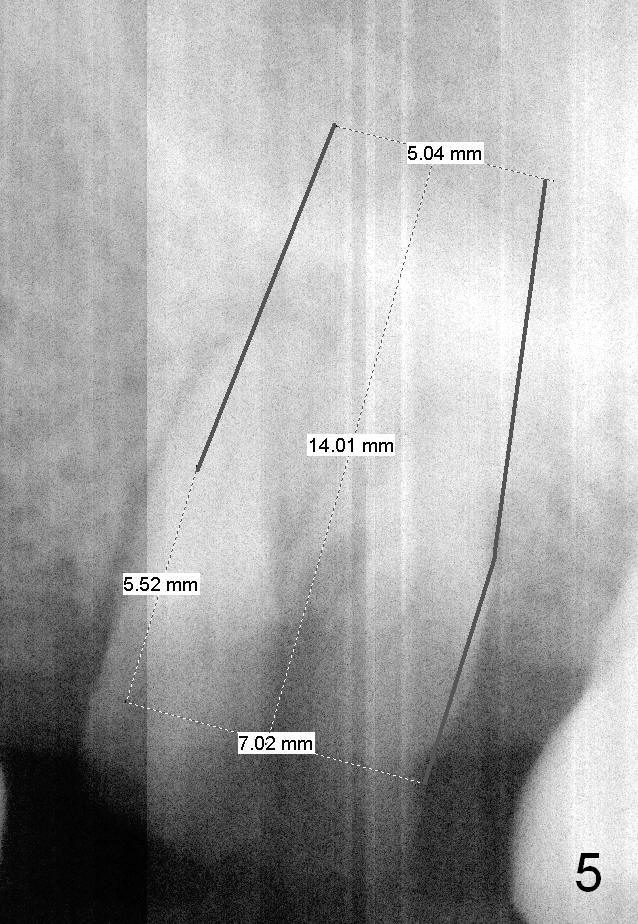

A 49-year-old man requests to restore #14 with residual roots (Fig.1). There is periapical radiolucency (Fig.2 *). A 5.9x10 mm bone-level implant is placed with minor sinus lift (Fig.3), whereas a short (Fig.4) or long (Fig.5) tissue-level implant is placed without or with sinus lift. The implant could be as large as 7 mm (Fig.5) to prevent post-extraction ridge atrophy.